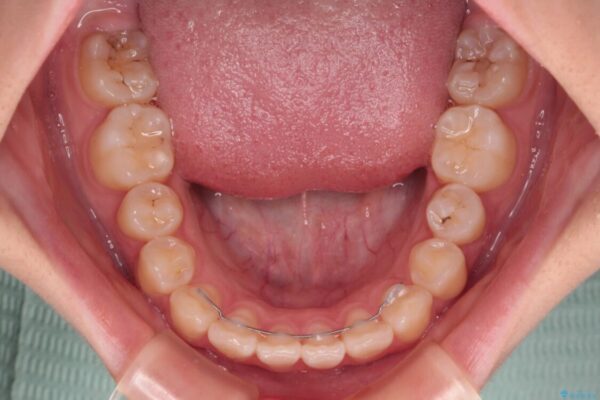

上下前歯のねじれを気にして来院された患者様です。

治療後

• インビザラインは使える自信がない ワイヤー装置にて矯正治療 治療後画像